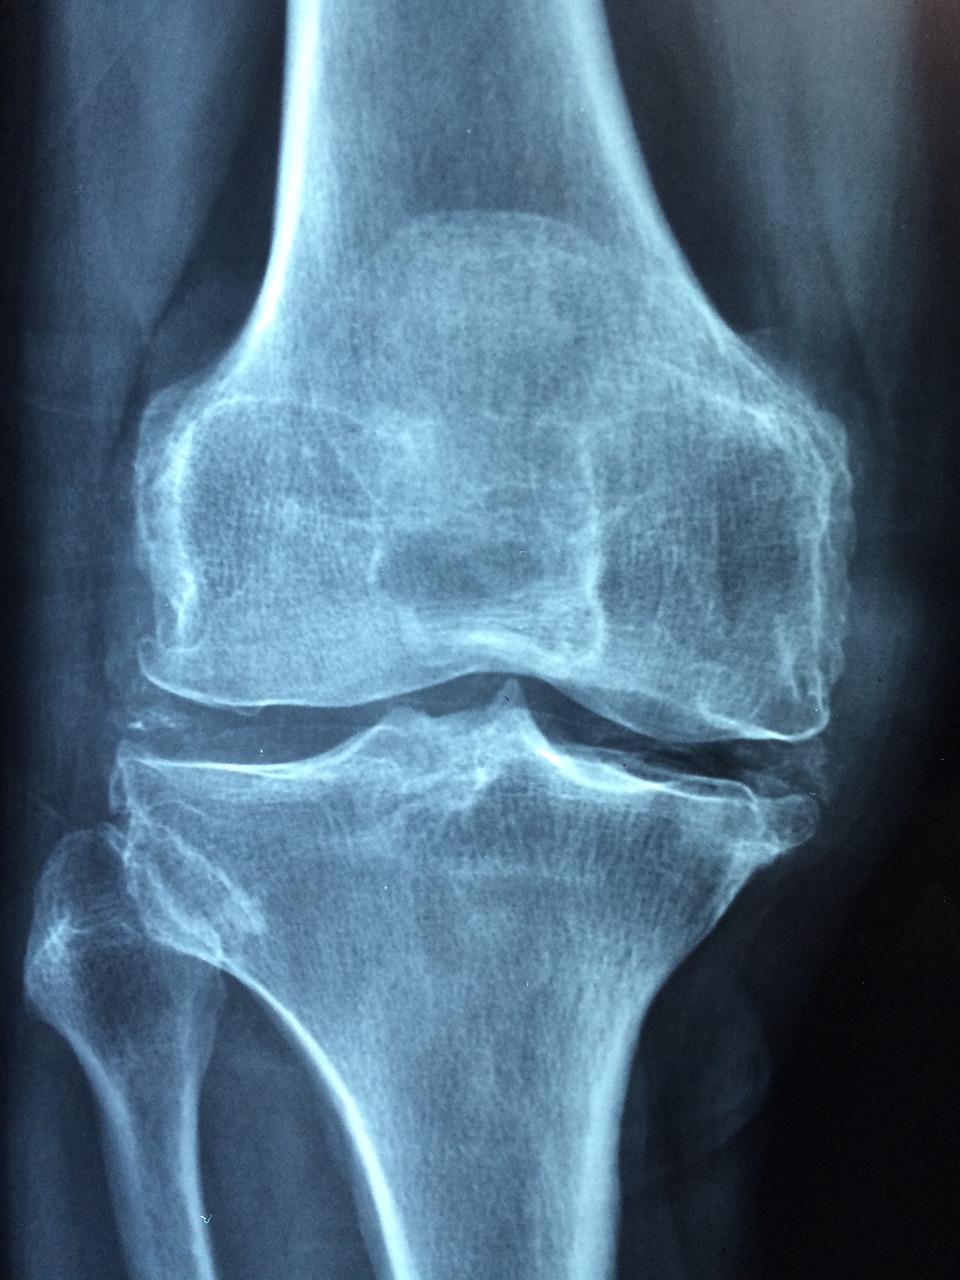

1. 이중에너지 X선 흡수계측법 (DXA)의 원리 및 측정 부위: 측정 원리: DXA는 서로 다른 두 가지 에너지 수준의 X선 빔을 인체에 투과시켜, 뼈와 연부 조직에 흡수되는 정도의 차이를 이용하여 골밀도를 측정하는 방식입니다. 낮은 에너지의 X선은 연부 조직에 더 많이 흡수되고, 높은 에너지의 X선은 뼈에 더 많이 흡수되는 원리를 이용합니다. 이 두 에너지 수준에서의 X선 감쇠량을 측정하고 연부 조직의 영향을 보정함으로써, 특정 부위 뼈의 단위 면적당 미네랄 함량(g/cm²)을 정량적으로 계산해냅니다. 주요 측정 부위: 골다공증성 골절이 흔히 발생하는 부위이자 예후에 중요한 영향을 미치는 부위를 중심으로 측정합니다. 요추 (Lumbar spine): 주로 제1요추에서 제4요추(L1-L4)까지의 평균 골밀도를 측정합니다. 척추는 해면골(trabecular bone)의 비율이 높아 골 대사가 활발하며 골밀도 변화를 민감하게 반영하지만, 퇴행성 변화(골극 형성, 추간판 간격 협소, 대동맥 석회화 등)로 인해 실제보다 골밀도가 높게 측정될 수 있는 단점이 있습니다. 대퇴골 근위부 (Proximal femur): 대퇴골 경부(femoral neck), 전자부(trochanter), 그리고 전체 고관절(total hip) 부위의 골밀도를 측정합니다. 이 중 대퇴골 경부 골밀도는 고관절 골절 위험 예측에 가장 중요한 지표로 간주됩니다. 전완부 (Forearm): 주로 요골의 원위 1/3 지점(distal 1/3 radius)을 측정하며, 요추나 대퇴골 측정이 불가능하거나 부갑상선 기능 항진증이 의심되는 경우, 또는 매우 비만하거나 마른 환자에게 유용할 수 있습니다.

4. 골밀도 측정의 한계점 및 고려 사항: 골밀도 측정은 골다공증 관리의 핵심적인 도구이지만, 몇 가지 내재적인 한계점을 가지고 있어 결과 해석 및 임상 적용 시 주의가 필요합니다. 뼈의 질(Bone Quality) 미반영: DXA는 뼈의 양적인 측면, 즉 미네랄 함량만을 측정하며, 뼈의 미세구조(골소주 연결성, 피질골 두께 등), 재형성률, 무기질화 정도, 미세손상 축적과 같은 뼈의 질적인 요소는 직접적으로 평가하지 못합니다. 뼈의 강도는 뼈의 양뿐만 아니라 질에도 크게 좌우되므로, 골밀도가 동일하더라도 뼈의 질에 따라 골절 위험은 달라질 수 있습니다. 측정 부위의 제한성: DXA는 특정 부위(주로 요추, 대퇴골)의 2차원적인 골밀도를 측정하므로, 전신 골격의 상태를 완벽하게 대표하지 못할 수 있습니다.

또한, 해면골과 피질골의 비율이 다른 부위의 골밀도 변화를 정확히 반영하지 못할 수도 있습니다. 퇴행성 변화 및 인공물의 영향: 특히 요추 부위에서는 퇴행성 척추 질환(골극 형성, 추간판 협소, 척추체 변형), 대동맥 석회화, 압박 골절 등으로 인해 실제보다 골밀도가 높게 측정될 수 있습니다. 수술 기구나 인공 삽입물도 측정에 영향을 줄 수 있습니다. 기기 및 측정자 간 오차: 서로 다른 DXA 기기 간에는 측정값에 차이가 있을 수 있으며, 동일 기기라도 측정자의 숙련도나 환자 자세 고정 등에 따라 오차가 발생할 수 있습니다. 따라서 추적 검사는 가능한 동일한 기기를 사용하고, 정기적인 정도 관리(quality control)가 중요합니다.